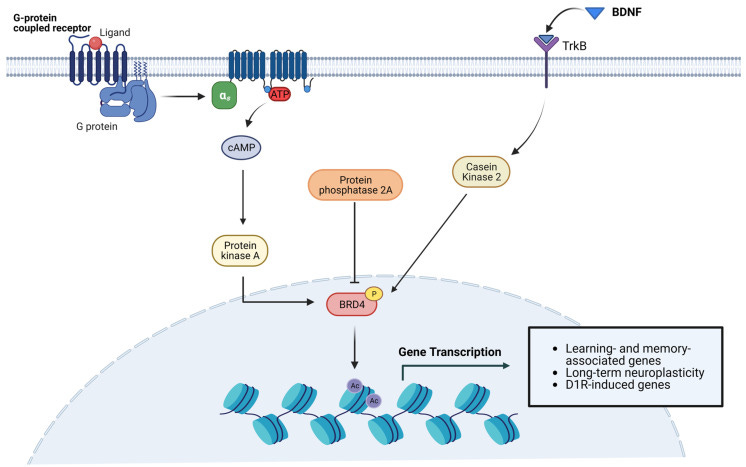

Though incomplete, some evidence has shed new light into the molecular pathways linking BRD4 and neuronal activity (Figure 2). Indeed, neurotransmitter and neurotrophic factors induce signaling cascades leading to the activation of PKA and Casein Kinase 2 (CK2). These kinases, in turn, phosphorylate BRD4, favoring its binding to acetylated histones [15,45,66].

Again, disruption of BET proteins up or down may induce all manner of pathologies, the authors note that this work deserves further investigation:

Another study documented elevated abundance of Brd4 mRNA in rat striatal neurons, where BRD4 is involved in dopamine-induced and cAMP/PKA-dependent basal transcription. Indeed, cAMP/PKA signaling elicits BRD4 recruitment to genes induced by dopamine stimulation, whereas pharmacological or genetic inactivation of BRD4 significantly downregulates the transcription of a subset of genes mediated by D1R [66]. Consistent with the role of BRD4 in dopaminergic signaling, Brd4 transcript levels are much higher than Brd2 and Brd3 in nucleus accumbens (NAc), a region enriched in D1R- and D2R-expressing neurons implicated in reward mechanisms [67]. This finding is further supported by the reportedly high concentration of BET proteins in the amygdala and midbrain, also involved in reward behavior in both rodents and non-human primates [52]. Other remarkable differences in the expression of specific BETs have been detected in some neuronal subtypes. For instance, Brd2 expression is prevalent in cerebellar neurons, while the highest Brd4 levels were found in claustral neurons of the frontal cortex and in some hippocampal neurons [65].